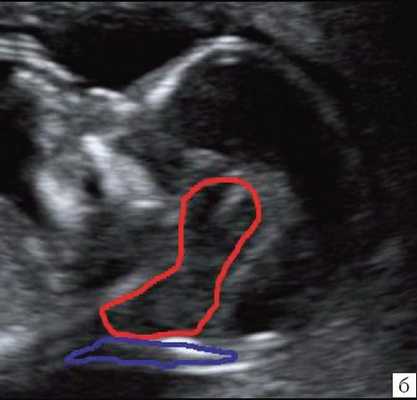

При изучении анатомии головного мозга плода в режиме 2D с применением стандартных аксиальных срезов во всех наших случаях мозжечок выглядел в виде овального образования однородной структуры с поперечным размером, менее уровня 5 процентиля для соответствующего срока беременности. При этом отсутствовала межполушарная выемка и область повышенной эхогенности по срединной линии мозжечка, характерная для отражения червя (рис. 1). На коронарном срезе также обращала внимание округлая однолобарная форма гипоэхогенного мозжечка (рис. 2). Использование трансвагинального подхода позволяло визуализировать дополнительно волокнистые структуры субарахноидального пространства (рис. 2).

Рис. 2. Корональные срезы головного мозга плода. Показан овальный контур мозжечка и волокнистые структуры субарахноидального пространства (стрелки).

а) Наблюдение 1, 3D.

б) Наблюдение 4, трансвагинально.

Анализ сохраненных трехмерных изображений позволил получить более детальные характеристики структур мозга плодов с РЭС. На среднесагиттальном срезе в наблюдениях 1, 2 и 4 (в наблюдении 3 получить качественно этот срез не удалось) отмечено наличие атипичной полукруглой формы шатра (fastigium) 4-го желудочка, гипоэхогенная структура мозжечка с контрастирующим наружным контуром (рис. 3). При этом в первых трех наблюдениях отмечено полное отсутствие структур червя, тогда как в наблюдении 4 по контуру 4-го желудочка выявлены гиперэхогенные структуры, расцененные как передние отделы червя. Наличие передних отделов червя отражает и ряд послойных срезов в режиме TUI (рис. 4). У плода в наблюдении 4 также обращает на себя внимание относительное расширение надмозжечковой цистерны, с линейными структурами, при нормальной ориентации намета мозжечка (рис. 4).

а) Наблюдение 2, 3D. На эхограмме: 1 - боковой желудочек, 3v - 3-й желудочек, стрелки - контур мозжечка, пунктирная линия - шатер.

б) Наблюдение 4. На эхограмме: М - мозжечок.

На эхограмме: М - мозжечок, 4v - четвертый желудочек, короткие стрелки - фрагменты червя.